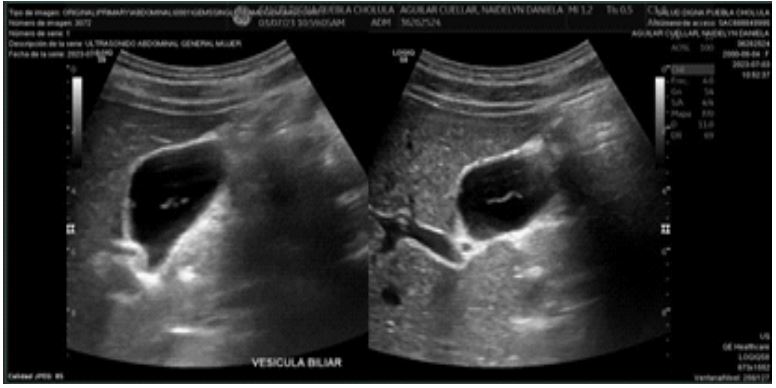

Radiological description

- Liver: Normal contours and echogenicity, homogeneous ultrasound pattern, no intrahepatic bile duct dilation.

- Common bile duct: 1 mm diameter, portal vein: 6.8 mm diameter.

- Gallbladder: Normal shape and contours, dimensions 51x20x24 mm (longitudinal, anteroposterior, transverse), wall thickness 2.4 mm. An intravesicular image was observed: anterior wall hyperechoic, homogeneous, solid, regular contours, no color Doppler flow, immobile, measuring 2.9 mm.

Conclusion: Small polyp inside the gallbladder, echogenic linear image compatible with a nematode, probable biliary ascariasis (Figure 1).

Figure 1: Ultrasound image of biliary ascariasis.